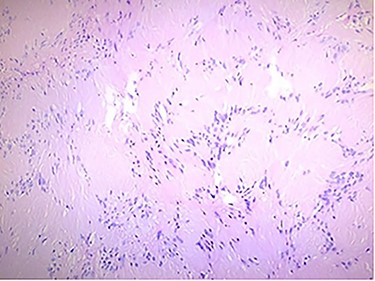

The histologic examination showed an Antoni A cellular pattern, composed of spindle cells with palisading nuclei areas, without mitotic activity or necrosis areas, being compatible with schwannoma (Fig. 3).

Histologic findings: the tumor was formed by spindle cells with elongated palisading nuclei; hematoxylin and eosin stain.